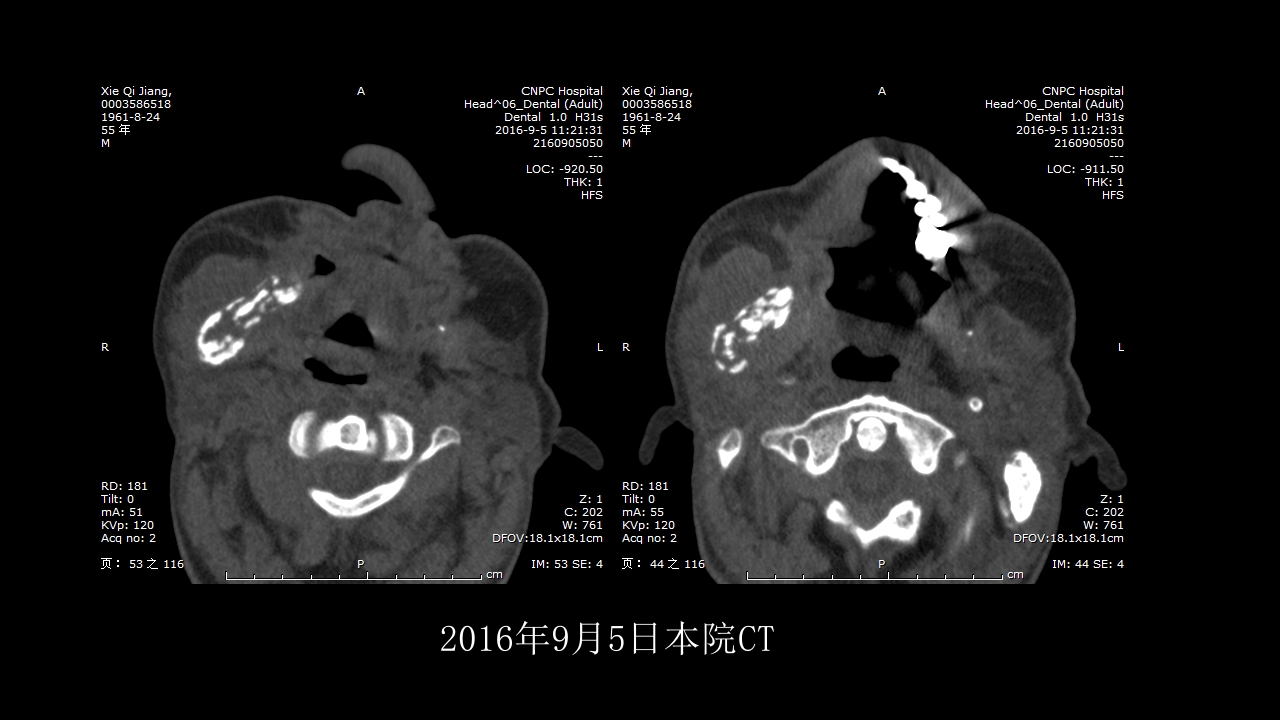

没有见过的弥漫性的骨质破坏